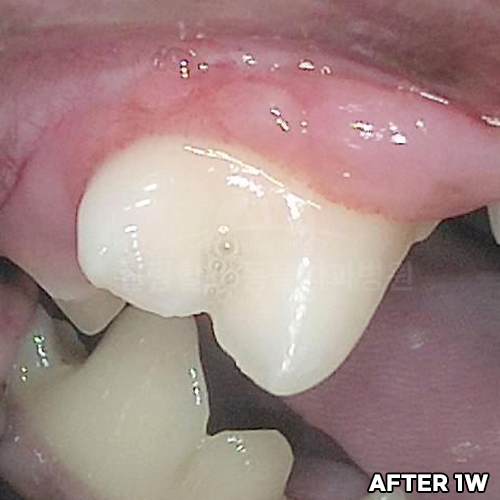

[강아지 치주치료 후 8개월 경과]